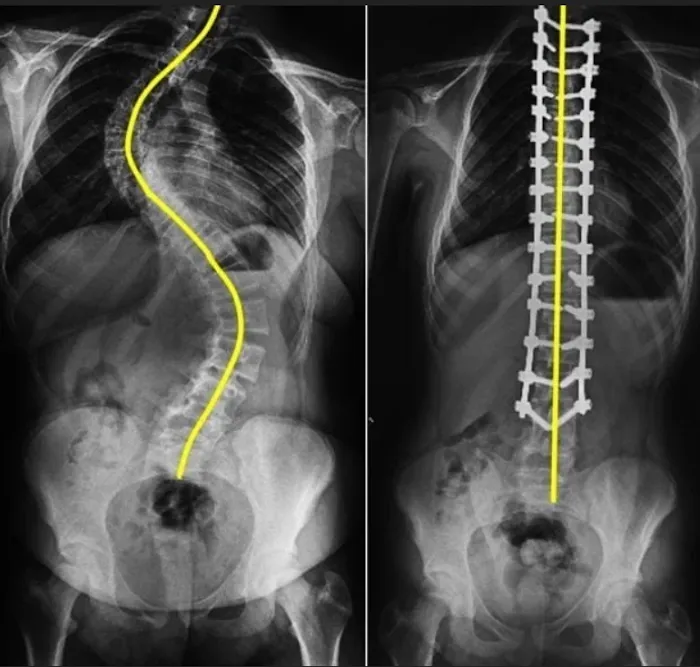

- Spinal Analysis and X-rays: As noted in customer reviews, the clinic uses X-rays to accurately diagnose misalignments, providing patients with a clear visual understanding of their condition.

- Empowering and Informative Consultations: As one reviewer noted, Dr. Chris helps patients feel "informed, empowered, and excited about my health journey." He takes the time to "walk me through everything" and explains the X-ray findings clearly.

- Scoliosis